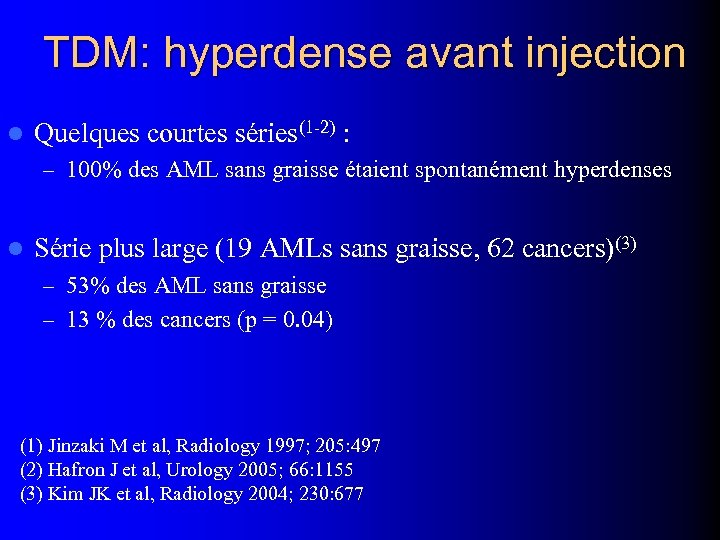

TDM: hyperdense avant injection l Quelques courtes séries(1 -2) : – 100% des AML sans graisse étaient spontanément hyperdenses l Série plus large (19 AMLs sans graisse, 62 cancers)(3) – 53% des AML sans graisse – 13 % des cancers (p = 0. 04) (1) Jinzaki M et al, Radiology 1997; 205: 497 (2) Hafron J et al, Urology 2005; 66: 1155 (3) Kim JK et al, Radiology 2004; 230: 677

TDM: hyperdense avant injection l Quelques courtes séries(1 -2) : – 100% des AML sans graisse étaient spontanément hyperdenses l Série plus large (19 AMLs sans graisse, 62 cancers)(3) – 53% des AML sans graisse – 13 % des cancers (p = 0. 04) (1) Jinzaki M et al, Radiology 1997; 205: 497 (2) Hafron J et al, Urology 2005; 66: 1155 (3) Kim JK et al, Radiology 2004; 230: 677